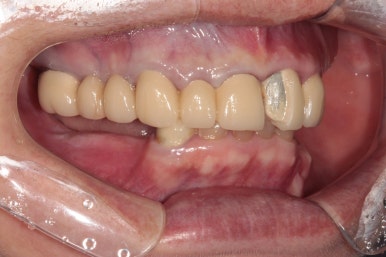

양옆으로 보았을 때도 아래 어금니는 모두 없어진 상태이고, 쓸수 있는 치아가 많지 않았어요.

왼쪽: 위턱, 아래쪽: 아래턱